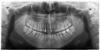

Уважаемые доктора интересует ваше мнение о кисте. Так же хотелось бы понять какие зубы наиболее проблемны. Чему уделить наибольшее внимание? Большое спасибо.

1. Киста на 11 зубе. Месяц назад стоматолог обнаружил гранулему, сказала "будем лечить, должна проийти в течении 4-8 месяцев". На данный момент 2 раза поменяли лекарство (каласепт) (1-ый раз положили на неделю, 2-й на месяц - еще стоит). Так же на десне есть свищик, он сильно уменьшился, но до конца не прошел. Действительно ли в моем случае гранулему есть шанс вылечить? Когда можно пломбировать канал?

2. Из-за гранулемы доктор депульпировал 21 зуб. Была ли в этом необходимость? Там стоит штифт?! (доктор не предупредила...) Его необходимость? Как пройден канал?

3. Так же есть необходимость заменить пломбу в 21 зубе? Нужна ли перепломбировка канала?

4. Болит 36 или 37 зуб, (слева снизу на снимке) доктор не определила.

5. 38, 48 прикрыты десной, ее иссечь надо?

7. Укажите пожалуйста на др. кариозные области и проблемы полости рта.